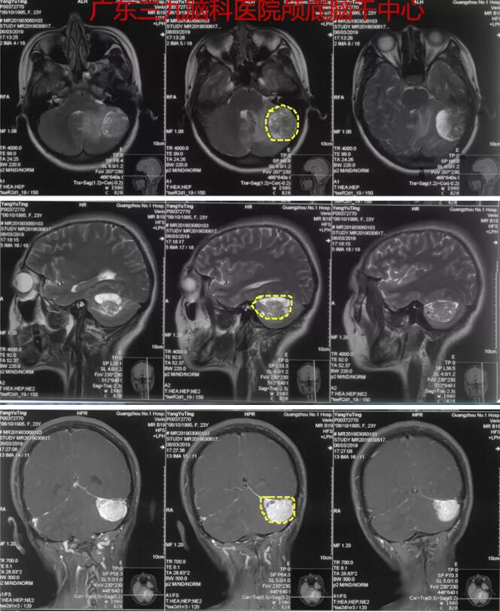

杨某,女,23岁,因“乳腺癌术后2年,间断头晕4个月”于2019年3月8日入院。患者无明显诱因出现眩晕呕吐,外院检查头颅MR示左侧桥小脑角区占位,为进一步诊治,转入广东三九脑科医院神经外一科。完善相关检查后3月12日全麻下为患者行“左侧桥小脑角区占位性病变切除术”,术程顺利,病理报告示: (左侧桥小脑区)孤立性纤维性肿瘤/血管周细胞瘤。

图1:术前MR示左侧小脑占位性病变,与天幕、乙状窦关系密切,结合病史(乳腺癌术后2年),考虑转移瘤可能性大,不除外脑膜瘤可能

图2:术后CT及MR示肿瘤全切除